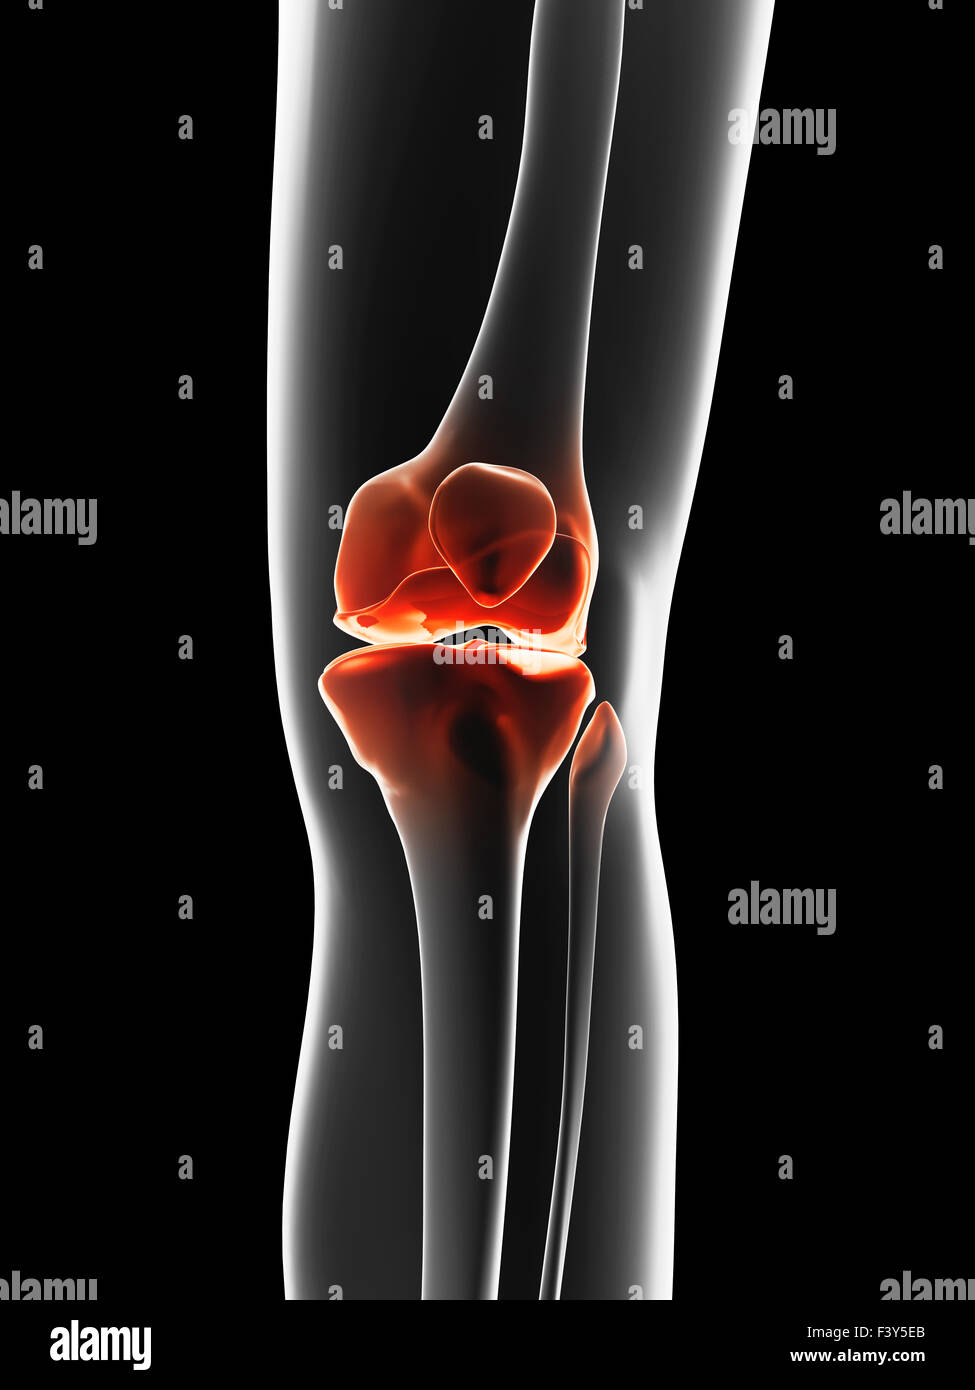

painful knee joint Stock Photo Alamy Floating Debris In Knee Joint You may also hear strange clicking sounds coming. This has been ongoing since the end of. loose bodies are another name for free floating pieces of debris in the joint. you may feel something floating in your knee joint because loose pieces of cartilage could be in there. a loose body is essentially a fragment of cartilage. Floating Debris In Knee Joint.

Knee joint anatomy. Front view of human knee with glowing effect Floating Debris In Knee Joint They are tissues that have torn away from their. one potential cause of knee pain is something called a “loose body.” knowing how to identify a loose body in your knee can help you seek out the right support when. a loose body is essentially a fragment of cartilage or bone that has broken away from the surface. Floating Debris In Knee Joint.